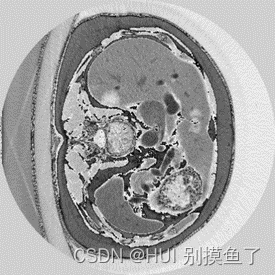

原发性肝癌诊疗知识

影像学检查是目前诊断微小肝癌和小肝癌的主要方法,临床上多采用超声、CT、MRI相结合的手段以提高检出率。其中,磁共振检查无辐射,对原发性肝癌的诊断更加精准,能够在早期对小肝癌进行诊断,提升患者的生存期和生活质量,因此具有重要的临床应用价值。此外,各影像手段的联合应用也是我们强调的一个重要维度,对患者进行精准的诊断,可以指导临床采取更合理科学的治疗方法。对于本次《原发性肝癌诊疗指南(2024版)》的更新亮点,影像组长曾蒙苏教授首先提到的是,磁共振检查对早期肝癌或小肝癌,甚至微小肝癌的重要性。